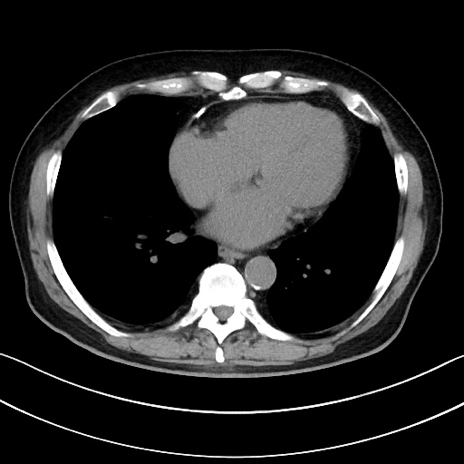

症例15(横断像)

【症例】70歳代男性

【主訴】腹痛

【現病歴】今朝から腹痛あり。全体的に痛い。特に左上の方。排ガスが今日はない。冷や汗が出る。

【既往歴】直腸癌術後

【身体所見】左側腹部〜上腹部に圧痛あり。腹膜刺激症状明らかなではない。軽度反跳痛。左下腹部に術後瘢痕あり。

【データ】WBC 7700、CRP 0.02